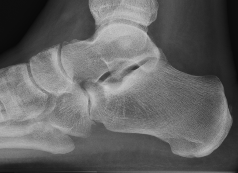

X-ray

Anteater sign

- oblique xray

- elongated process on calcaneum or prolongation of navicular